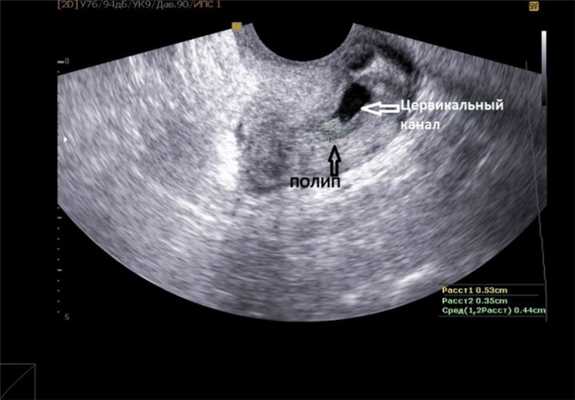

Ультразвуковое исследование (УЗИ) позволяет врачу увидеть утолщение внутреннего слоя матки (эндометрия), наличие полипов (выростов в полости матки). Во время гистероскопии в полости матки определяются разрастания различной величины и формы. Фиброзные полипы эндометрия имеют вид бледных единичных образований округлой или овальной формы, размер которых варьирует от 0,5×1 до 0,5×1,5 см, расположенные на ножке.

При гинекологическом осмотре в зеркалах можно обнаружить полипы шейки матки, в то время как полипы эндометрия обычно недоступны визуализации и пальпации. При проведении УЗИ малого таза обращает внимание наличие расширенной полости матки, утолщенного эндометрия с четкими разрастаниями слизистой однородной структуры.